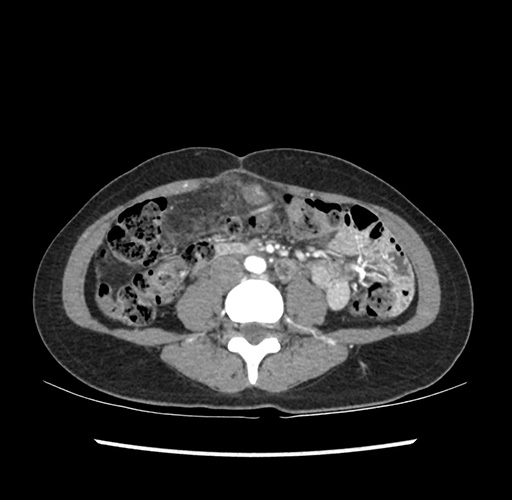

Imaging Analysis

Look through the patient's CT scan to identify any areas of concern for the necessary procedure.

Based on your CT findings, which issue(s) would give reason for "planned slowing down moment(s)" in this case?